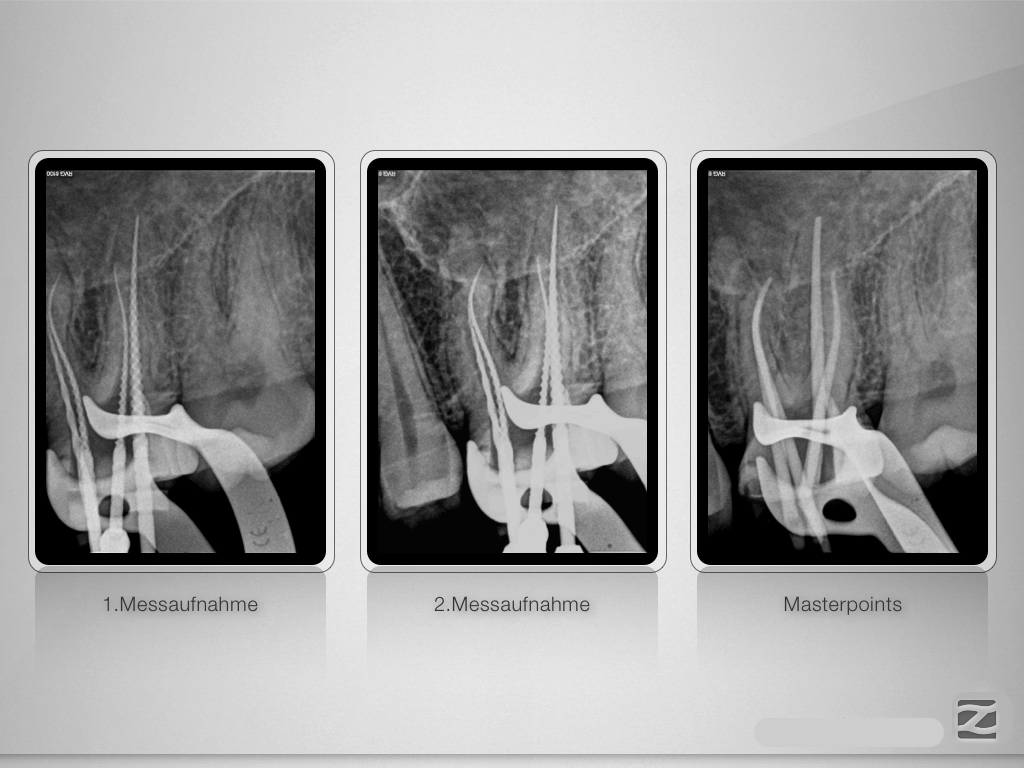

26D.004

Entwarnung